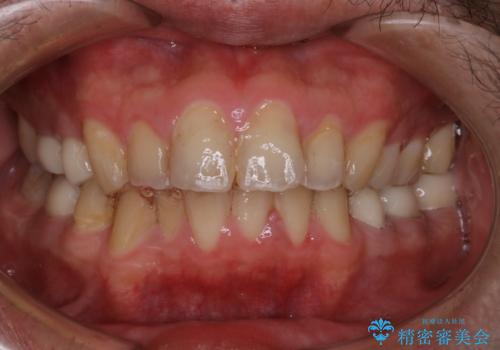

インビザライン矯正治療のスキャニング前のPMTC

- インビザラインでのスキャニング前にPMTCを希望されました。PMTC60分コースを行いました。

矯正治療前には、PMTCで歯石や汚れを取り除き、健康的な歯肉の状態にすることが大切です。PMTCでは、がたつきになどより、ご自身では取り切ることのできない細かい部分などに付着した汚れなども、専門的な機械や材料を使用してクリーニングを行います。

また、しっかりと汚れを除去することで、虫歯や歯周病などを早期発見することができます。